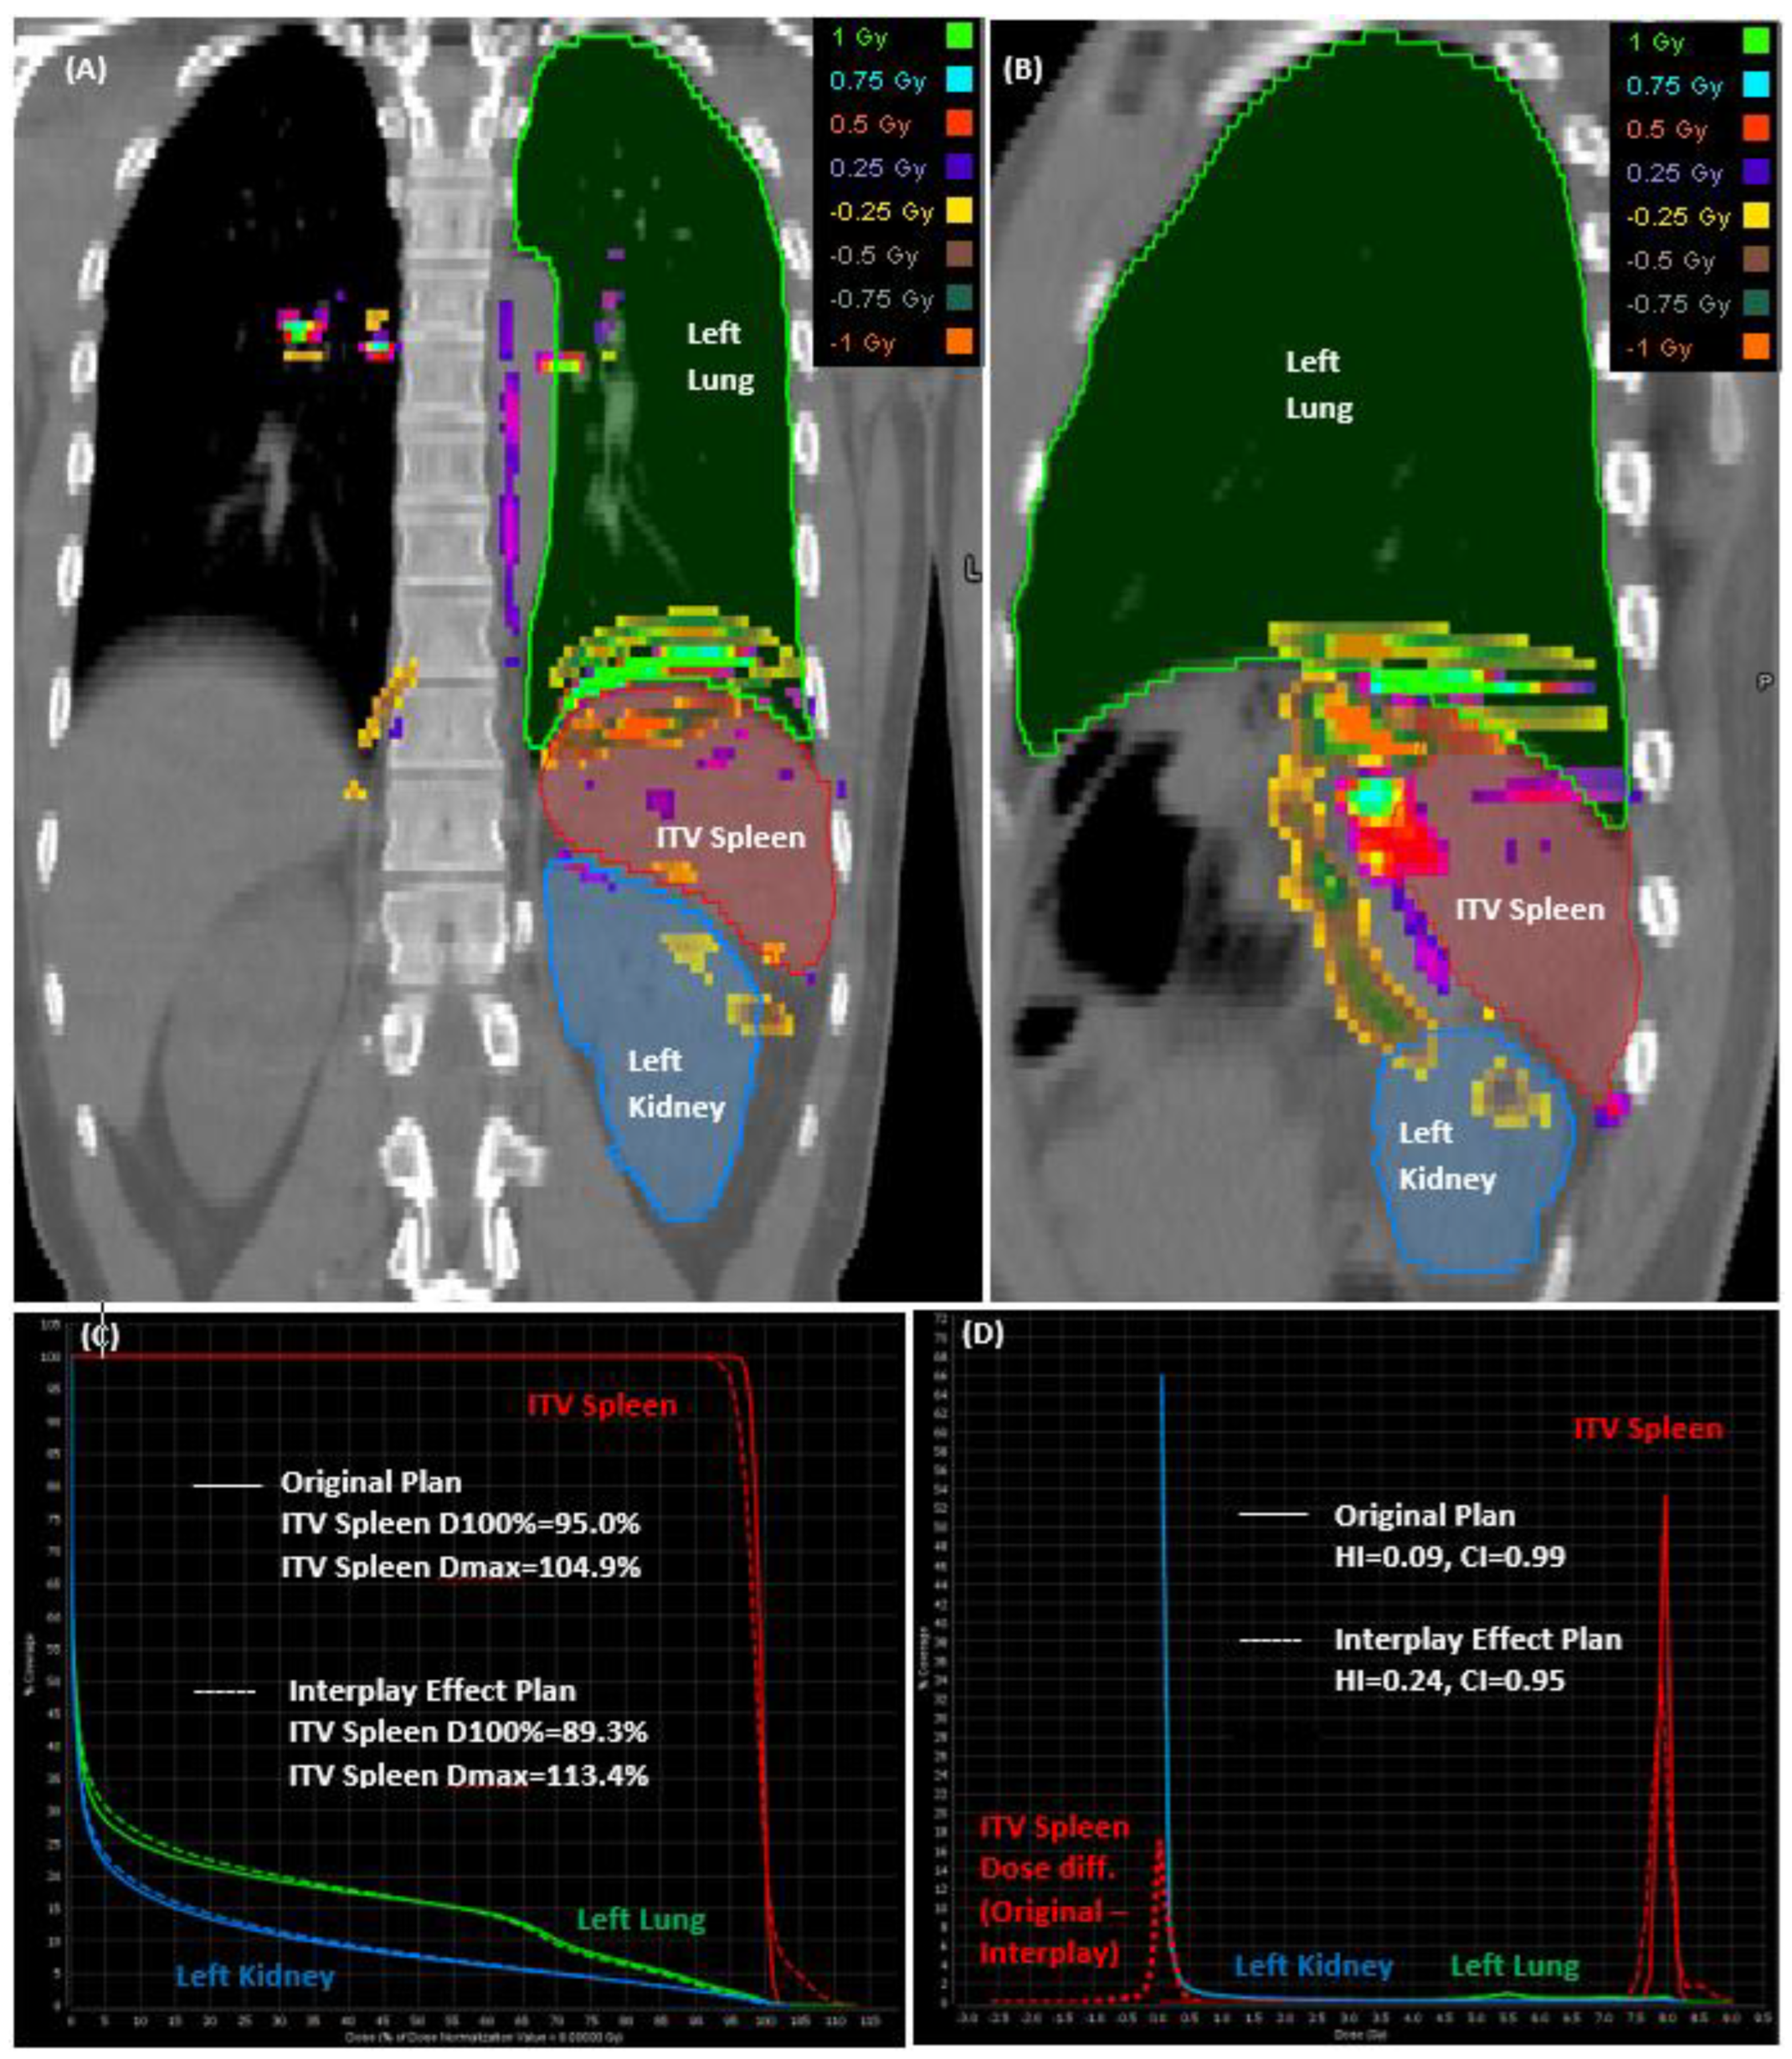

Figure 4 illustrates the dose subtraction performed between the original and interplay effect plans, depicted across the coronal (Figure 4A) and sagittal (Figure 4B) planes. Additionally, it displays the cumulative (Figure 4C) and differential (Figure 4D) dose volume histograms (DVH) for patient case #9, wherein a splenic motion of 10 mm was measured. While the normal organs of the left lung and left kidney displayed comparable results in the DVH curves for the original and interplay effect simulation plans, ITV spleen exhibited significant variations with noticeable cold and hot regions evident in the lower and higher dose levels depicted in the cumulative DVH curves.

In the differential DVH curves plotted in Figure 4D, the dose distributions within specific volume intervals of ITV spleen are depicted, providing insight into how the dose was distributed across the same ITV spleen volume for both the original and interplay effect plans. The assessment of homogeneity index (HI) and conformity index (CI) indicated that the original plan displayed greater homogeneity (HI = 0.09) and more conformal dose distributions (CI = 0.99). Conversely, the interplay effect plan experienced proton range errors, leading to the presence of both cold and hot regions with a reduced homogeneity (HI = 0.24) and slightly lower conformity (CI = 0.95). Upon evaluating the dose subtraction between the original and interplay effect plans, the analysis revealed a mean dose difference of 0.03 ± 0.21 Gy-RBE within the range of +0.74 and −1.29 Gy-RBE for the ITV spleen volume. Notably, 1% of the volume suffered from at least ±0.5 Gy-RBE dose discrepancy (or 6.25% of Rx = 8 Gy-RBE), resulting in hot and cold regions in the ITV spleen volume.

Figure 4. The dose subtraction between original and interplay effect plan seen from the coronal (A), and sagittal (B) planes, as well as the cumulative (C) and differential (D) DVHs of patient case #9 with 10 mm of splenic motion.